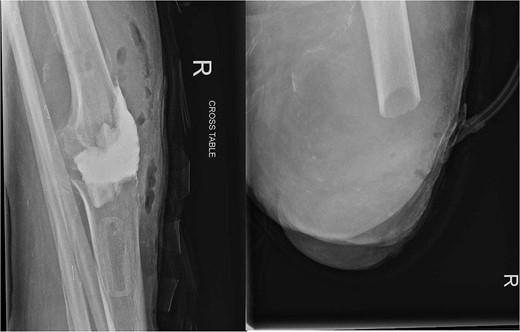

In July 2023, a 75-year-old female patient underwent elective right total knee replacement with patellar resurfacing for osteoarthritis (Fig. 1). Prior to this procedure she was able to mobilize using a walker. Her comorbidities included hypertension, type 2 diabetes mellitus, diverticulosis, Parkinson’s disease, and a body mass index of 33.2. Surgery was uneventful so she was discharged home and requested to continue with rehabilitation (Fig. 2). Two weeks postoperatively she noticed redness and warmth surrounding the knee joint and a further 2 weeks later she felt a “pop” whilst walking. She then presented with a painful, swollen right knee on which she was unable to weight bear. X-rays identified a closed right patellar sleeve fracture. It was assumed that the pain and inflammation was due to the fracture and not due to infection and the decision was taken to treat the fracture non-operatively. The knee was splinted, and she was allowed to touch weight bear with a frame.

Over the following month, the skin above the fractured patella became necrotic, resulting in an open discharging wound. It was now clear that infection was the issue. With Orthoplastics involvement, she underwent multiple tissue samplings, patellectomy, removal of implants, and insertion of an antibiotic impregnated cement spacer (Fig. 3). Over the ensuing days the infection was uncontrollable despite further debridement and appropriate multi-drug antibiotic therapy. Following a multi-disciplinary team decision, a staged Above Knee Amputation (AKA) was performed (Fig. 3) with negative pressure dressings applied in the interim. Patient was discharged 4 weeks later on achieving closure of the stump. Mobility at discharge was limited to hoist transfers. Unfortunately, the patient passed away 8 weeks later.

On the left X-ray of the knee after removal of prosthesis and insertion of antibiotic-impregnated cement spacer and on the right X-ray of the stump following amputation.